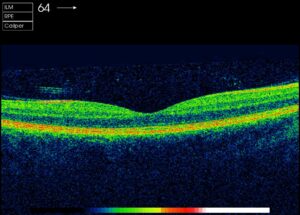

Die Netzhautschichten sind regelmäßig dargestellt. Zentral zeigt die Einsenkung die Stelle des schärfsten Sehens (Fovea) an.

Optische Cohärenztomographie OCT

Das OCT ist inzwischen der Goldstandard in der Beurteilung von Makulaerkrankungen. Sowohl die Diagnose als auch die Verlaufsbeurteilung und nicht zuletzt der Behandlungserfolg der Therapie hängen maßgeblich davon ab.

Auch die Dicke der Nervenfaserschicht im Bereich des Sehnerven kann hochauflösend dargestellt und vermessen werden, ein wichtiges diagnostisches Maß bei Sehnerverkankungen.